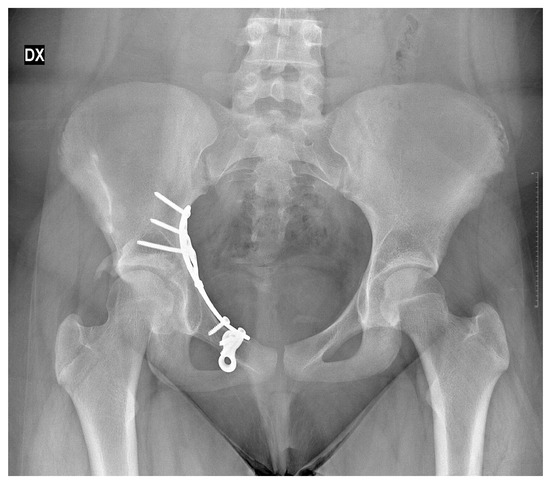

Subsequent clinical and radiographic follow-up visits were conducted at approximately 3 months, 6 months, and 4.5 years after definitive fixation hip (last X-ray was performed at 30 months follow-up). After 30 months, no further X-ray examinations were performed in order to avoid exposing the patient to unnecessary radiation for diagnostic or therapeutic purposes (Figure 5, Figure 6 and Figure 7).

Figure 7.

X-rays follow-up at 30 months by the surgical treatment. DX = Right.